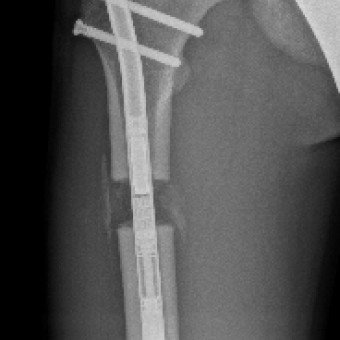

Die Knochenverlängerung mit dem magnetgetriebenen Marknagel Precice® hat sich als bedeutendste technologische Innovation in der Extremitätenrekonstruktion etabliert. Bei dieser Methode wird der getrennte Knochen durch Callusdistraktion täglich um etwa 1 mm verlängert. Im Vergleich zu externen Fixateuren ist diese vollimplantierte Lösung für Patientinnen und Patienten deutlich angenehmer und weniger schmerzhaft.

Die Ergebnisse sind ausgezeichnet und Komplikationen selten. Im schweizerischen Vergleich gehören wir auf diesem Gebiet zu den führenden Kliniken.